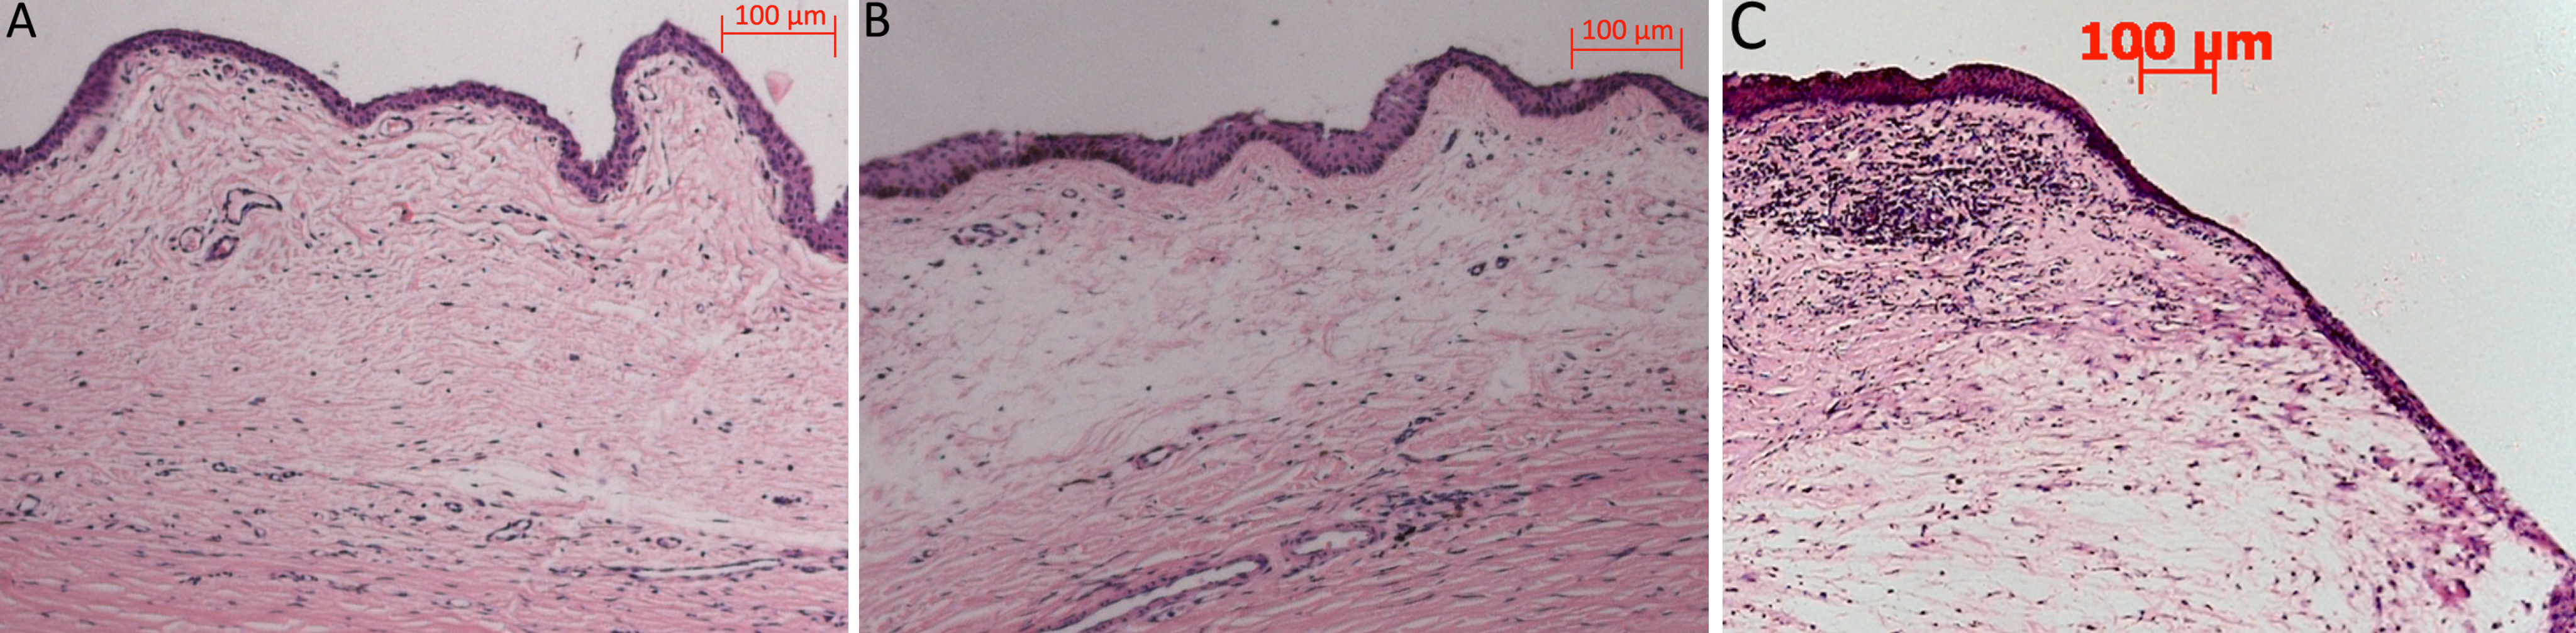

Figure 6. Histologic characteristics of

the surgical site associated with the PBS group, siRNA group, and MMC

group on day 60 after surgery. Treatment with IKKβ-siRNA (B)

showed a marked reduction in subconjunctival scar tissue compared with

the PBS group (A). The conjunctival epithelium appeared healthy,

and the subepithelial connective tissue was loosely arranged, with

moderate subconjunctival cavities, while the MMC treated eyes (C)

exhibited

marked acellularity and large bleb cavities.